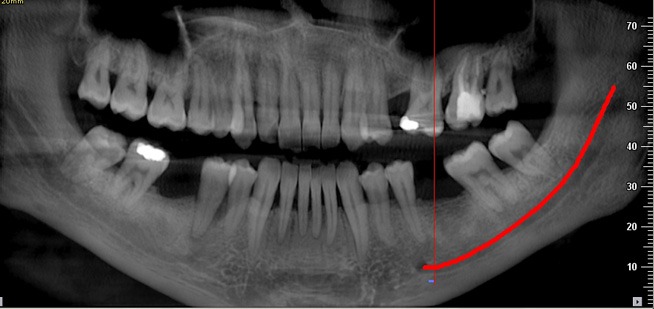

Endo-Perio

Der Facharzt für Endodontie und Periodontologie benötigt Bilder von absoluter Spitzenqualität und Detailschärfe, um Verfahren wie die Behandlung von Zahnbrüchen, die Heilung von Zahngewebe und die Therapie des Kieferkanals vorzunehmen, da er über genaue Details der behandelten Zone und des Krankheitsbilds verfügen muss, um eine wirkungsvolle Behandlung planen zu können. Nur eine eingehende Untersuchung der betroffenen Areale kann Aufschluss über einen mehr oder weniger invasiven Eingriff geben.